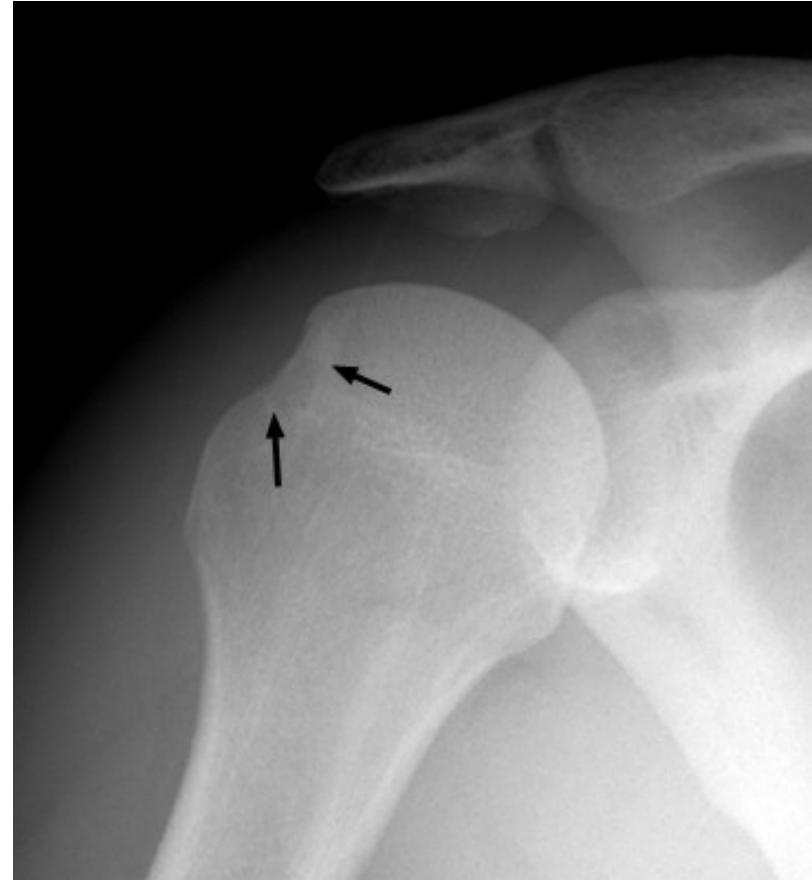

Elbow/Shoulder Dislocation

- Shoulder Dislocation Signs:

- Hill-Sachs Deformity: Compression fracture of the posterior humeral head. - recurrent anterior shoulder dislocation. (2nd image)

- Bankart Lesion: an anterior dislocation of shoulder - Injury to the anterior glenoid labrum. (3rd)